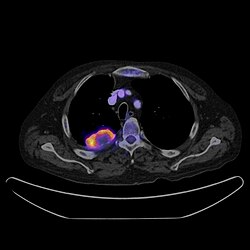

PET CT

Positron emission tomography–computed tomography is a hybrid CT modality which combines, in a single gantry, a positron emission tomography (PET) scanner and an X-ray computed tomography (CT) scanner, to acquire sequential images from both devices in the same session, which are combined into a single superposed (co-registered) image. Thus, functional imaging obtained by PET, which depicts the spatial distribution of metabolic or biochemical activity in the body can be more precisely aligned or correlated with anatomic imaging obtained by CT scanning.[24]

PET-CT gives both anatomical and functional details of an organ under examination and is helpful in detecting different type of cancers.[25][26]